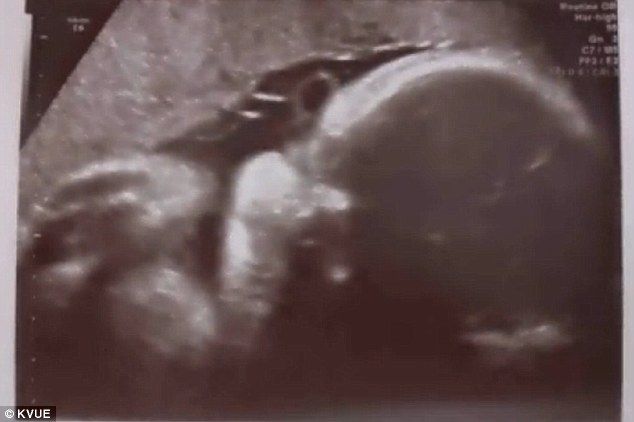

Έγκυος γυναίκα, στην οποία διαγνώστηκε καρκίνος του μαστού τρίτου επιπέδου την προηγούμενη εβδομάδα, έφερε στον κόσμο το παιδί της, ένα αγοράκι, έναν μήνα νωρίτερα, ώστε να ξεκινήσει άμεσα χημειοθεραπείες.

Η Gretchen Bell από την Virginia Beach ήταν οκτώ μηνών όταν ο γιατρός της ανακάλυψε τον καρκίνο. Έτσι αναγκάστηκαν να αποφασίσουν αν θα προχωρούσαν άμεσα σε τοκετό ή θα περίμεναν δύο ακόμα εβδομάδες μέχρι το αγοράκι να είναι ασφαλές για να γεννηθεί. Τελικά, εφόσον η κατάσταση της μητέρας κρίθηκε σοβαρή, γέννησε νωρίτερα ώστε να ξεκινήσει άμεσα τις χημειοθεραπείες. Πράγματι έτσι συνέβη και ο μικρός γεννήθηκε, μικρός μεν, πολύ καλά στην υγεία του δε. Η άτυχη γυναίκα θα υποβληθεί άμεσα σε χημειοθεραπείες.